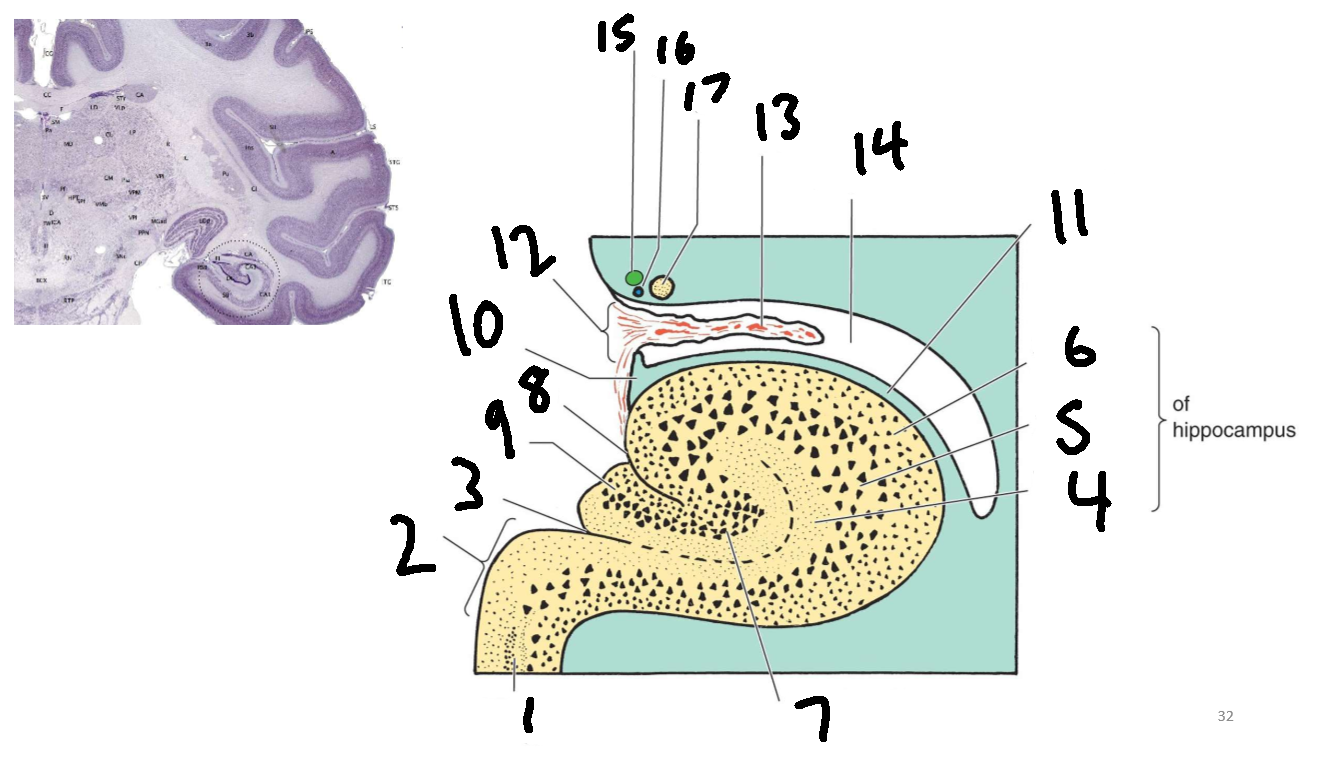

What structure is this?

hippocampus

What is 1?

hippocampus

What is 2?

rhinal sulcus

What is 3?

lateral ventricle

What is 4?

thalamus

What is 5?

entorhinal cortex

What is 6?

perirhinal cortex

What is 7?

parahippocampal cortex

What is 1?

gyrus dentatus

What is 2?

cornu ammonis

What is 3?

fimbria

What is 3’?

alveus

What is the arrow pointing to?

happicampal sulcus

What is ca1, ca2, ca3 and ca4?

fields of cornu ammonis

What is 4?

tela choroidea

What is 5?

stria terminalis

What is 6?

tail of caudate nucleus

What is 7?

temporal horn of lateral ventricle

What is 8?

collateral eminence

What is 9?

collateral sulcus

What is 10?

parahippocampal

What is 11?

entorhinal area

What is 12?

subiculum

What is 13?

lateral geniculate body

What is 1?

parahippocampal gyrus

What is 2?

subiculum

What is 3?

hippocampal sulcus

What is 4?

molecular layer

What is 5?

pyramidal layer

What is 6?

polymorphic cell layer

What is 7?

granule cell layer of dentate gyrus

What is 8?

fimbriodentate sulcus

What is 9?

dentate gyrus

What is 10?

fimbria of hippocampus

What is 11?

alveus

What is 12?

choroid fissure

What is 13?

choroid plexus

What is 14?

temporal horn of lateral ventricle

What is 15?

stria terminalis

What is 16?

thalamostriate vein

What is 17?

tail of caudate nucleus